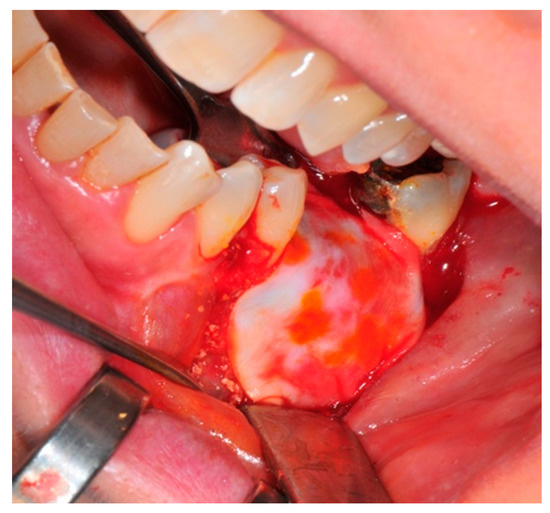

- Preparation of the receiving site: The exposed bone is cleaned from all of the remaining soft tissue and it is then prepared with multiple perforations using a small ball bur; this procedure is known as “bone refreshing” and it is performed to expose the cancellous portion of the residual bone, which shows a great osteo-genetic potential (Figure 6).